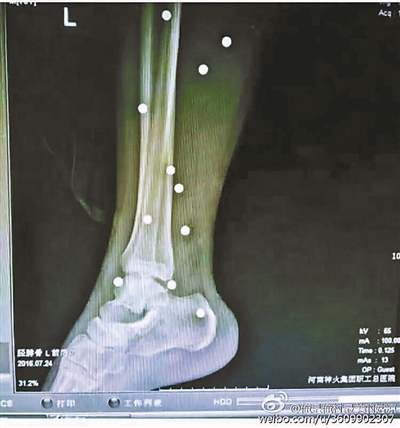

爆炸導(dǎo)致鋼珠遍布傷者身體各處

黃明的伯伯對北青報記者表示,由于黃明直接踩到了爆炸物,所以傷情最為嚴(yán)重,“他的腿被炸斷,身體內(nèi)被炸進了40多顆鋼珠。手術(shù)后已經(jīng)從體內(nèi)取出29顆鋼珠,還有十多顆鋼珠沒有取出來?!备鶕?jù)黃明的入院記錄,他全身有多處爆炸傷,且全身多處異物存留。

爆炸發(fā)生時,陳浩的位置與黃明靠得很近,因此也受傷較重。他告訴北青報記者,經(jīng)過10多個小時的手術(shù)后,醫(yī)生從他身體里取出了12顆鋼珠。目前,他和黃明兩人經(jīng)過手術(shù)后,已從重癥監(jiān)護室轉(zhuǎn)至普通病房。其余三人中,陳剛的臀部受傷,當(dāng)天晚上在醫(yī)院清理完傷口后便回了家,而同行的兩名女生身上有一些擦傷。